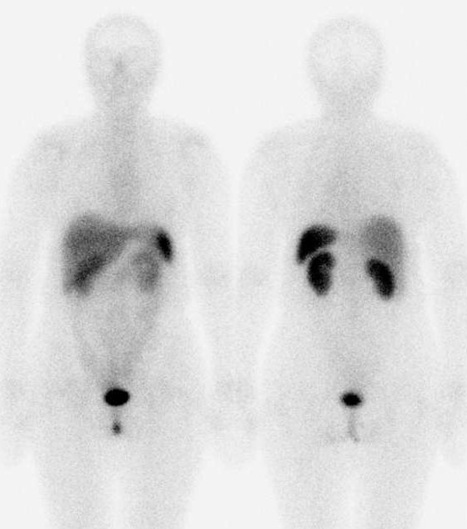

/ Obr. č. 1: Celotělová scintigrafie v přední a zadní projekci 5 hod. po aplikaci OctreoScanu/

/ Obr. č. 3: Celotělová scintigrafie v přední a zadní projekci 26 hod. po aplikaci OctreoScanu/

Při vyšetření za 5 hod. po aplikaci je patrná pouze fyziologická difuzní depozice radioaktivity v játrech, slezině, v ledvinách a močovém měchýři, ve střevech. Za 26 hod. je navíc nepříliš výrazné ložisko vyšší depozice radiofarmaka oválného tvaru ve střední čáře v mesogastriu, nález je suspektní pro přítomnost tkáně se zvýšenou hustotou somatostatinových receptorů v této lokalizaci. Nález je obdobný jako při vyšetření před necelými 4 roky.

58 letá nemocná trpí výraznými potížemi, které spolu s laboratorními výsledky podporují podezření na přítomnost karcinoidu. Také opakovaná scintigrafická vyšetření (před necelými 4 roky a nyní) pomocí Octreoscanu toto podezření dále podporují. Scintigrafický nález za 5 hodin je negativní, avšak zobrazuje se nepříliš výrazné ložisko ve střední čáře v mesogastriu za 26 hodin po aplikaci radioindikátoru.